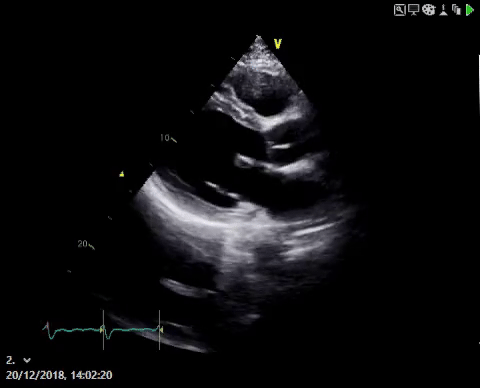

Patients with underlying heart conditions such as advanced heart failure or advanced cardiomyopathy may be at risk of dangerous heart rhythms. There are different ways to try and identify which of these patients are at highest risk and would benefit from an ICD. We know that in heart failure patients, weakening of their heart muscle can increase the risk of dangerous heart rhythms and this can be measured using an echocardiogram to take pictures of the heart as shown here.

the risk is proportional to the weakness of the heart muscle, measured using an echocardiogram as shown here. Patients with severely weakened heart muscles (quantified using the left ventricular ejection fraction (LVEF) of less than 35% AFTER all medication options have been tried to restrengthen the heart are considered highest risk and this was also the group studied in the trials above.